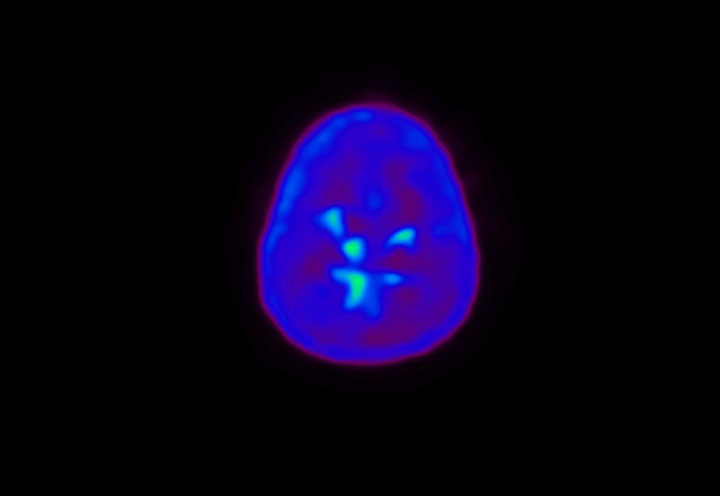

Head / Case4 : Amyloid

Sagittal

Courtesy : Kindai University Hospital

- Imaging protocol

- Injected dose: 3.21 MBq/kg, 18F-Flutemetamol

- Uptake time: 100 minutes

- Scan time: 20 minutes